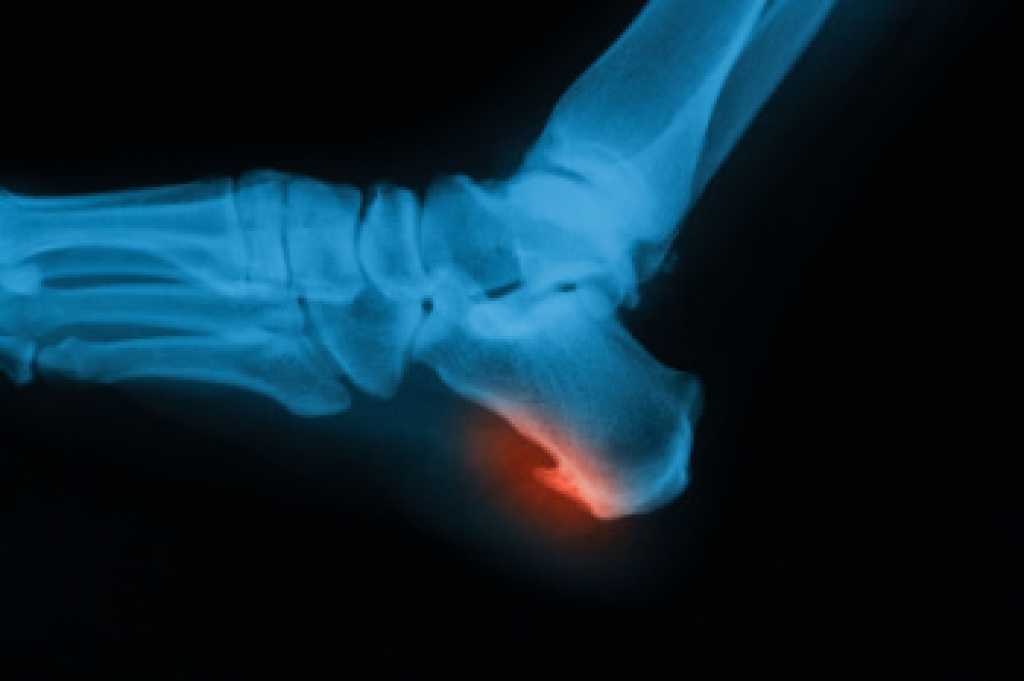

Custom orthotics are specialized shoe inserts created to support and align the feet according to each person’s unique structure and walking pattern. They are an effective way to relieve foot discomfort caused by conditions such as flat feet, high arches, plantar fasciitis, bunions, and heel pain. When the natural alignment of the foot is off balance, it can lead to pressure points, strain, and pain that affect how a person stands, walks, and moves. Orthotics work by redistributing weight evenly and supporting the arch to reduce stress on the muscles, tendons, and joints of the feet and lower legs.

Foot discomfort can develop for many reasons, including wearing improper footwear, long hours of standing, repetitive motion, or underlying structural problems. Over time, this discomfort can extend beyond the feet, contributing to knee, hip, or lower back pain. Custom orthotics help correct these issues by improving alignment and promoting more efficient movement. They are made using precise measurements and imaging to ensure the best fit for each patient, providing targeted support and cushioning where it is needed most.